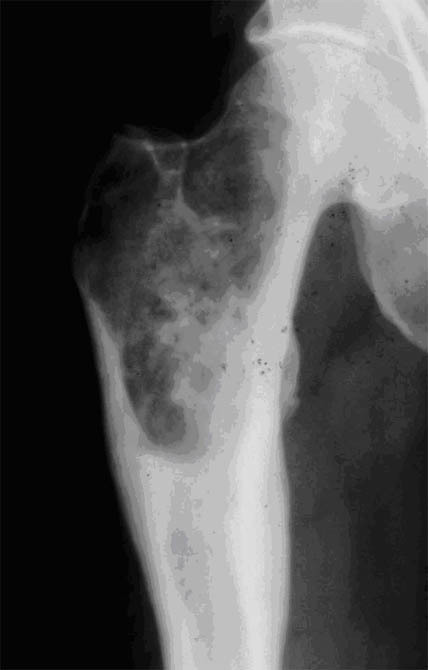

Quel est le stade Garden de cette fracture de l’ES du fémur? Quel est le risque évolutif principal?

Fracture ES fémur garden 4 car perte de contact entre fragments,

les travées osseuses sont normales

Risque max d’ostéonécrose aseptique